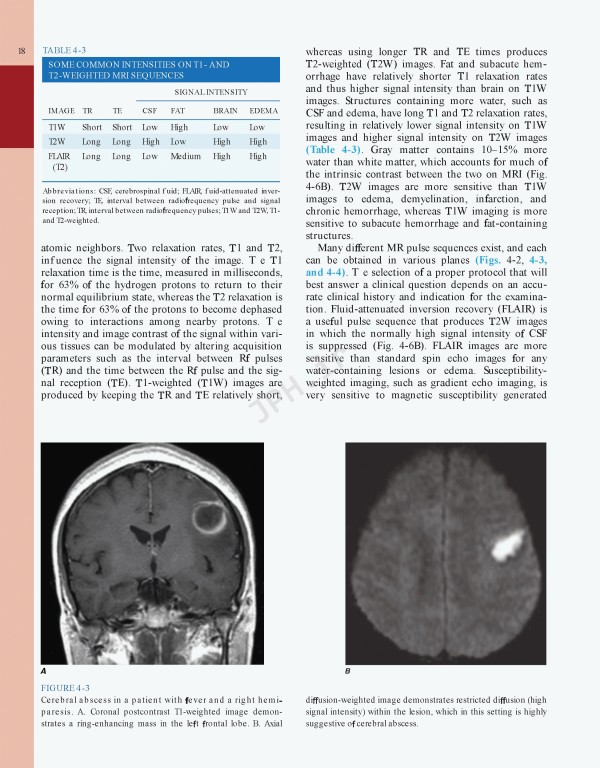

کتاب Harrisons Neurology in Clinical Medicine 4th edition | مغز و اعصاب در پزشکی بالینی هاریسون 2018 یک همراه بالینی مختصر و تمام رنگی که دارای مجموعه‌ای عالی از فصول مرتبط با نورولوژی برگرفته از اصول طب داخلی هریسون، نسخه نوزدهم می‌باشد.

• Extensively updated to highlight recent advances in the understanding, diagnosis, treatment, and prevention of neurologic and psychiatric disorders; expanded coverage of neurodegenerative diseases; extensively revised chapter on cerebrovascular diseases; the latest breakthroughs in sleep disorders and migraine

• Enhanced by numerous neuroimaging figures throughout the text and an expanded atlas of neuroimaging findings